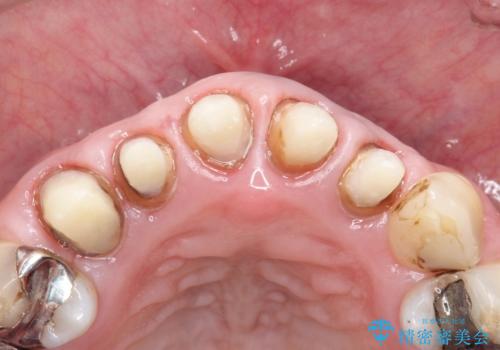

- 上の前歯の根元が黒くなっているので、再治療をしたいとのことで来院された患者様です。

レントゲンを撮影すると、適合不良のかぶせ物が装着されており、根の治療も不十分であることが確認されました。

適合不良のかぶせ物をすべて除去して、根の中の治療から再治療を行うこととなりました。

適合不良のかぶせ物が装着されていた歯は、内部がやはり虫歯になっていました。

かぶせ物だけではなく見えないところも、精密な治療をすることが重要となります。